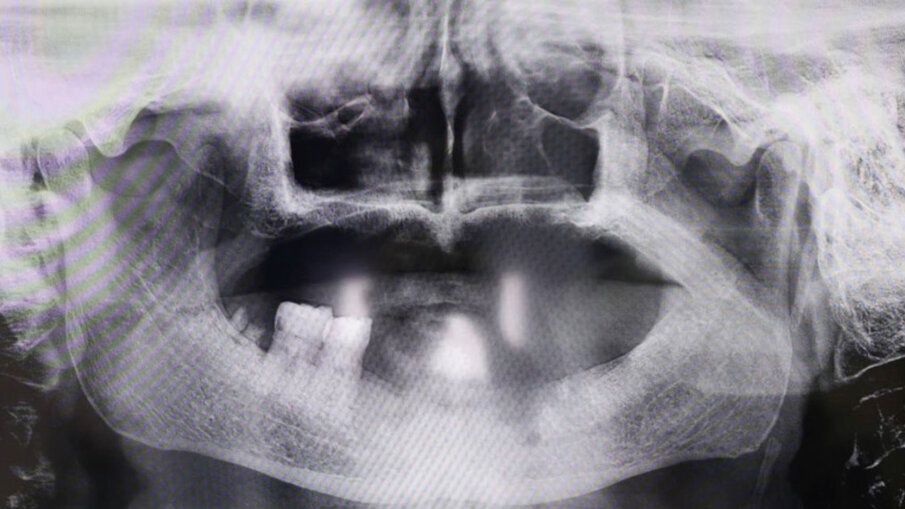

Fig. 3 - RX iniziale. Il Paziente ottantenne si presenta con una protesi mobile realizzata e inserita da oltre 20 anni. Il desiderio di avere i denti fissi non l’ha mai abbandonato. Dalla RX si evince la chiara assenza totale di osso, situazione che non permette l’inserimento degli impianti in titanio tramite intervento tradizionale. Questo caso è stato affrontato tramite l’inserimento del Premaxillary Device.